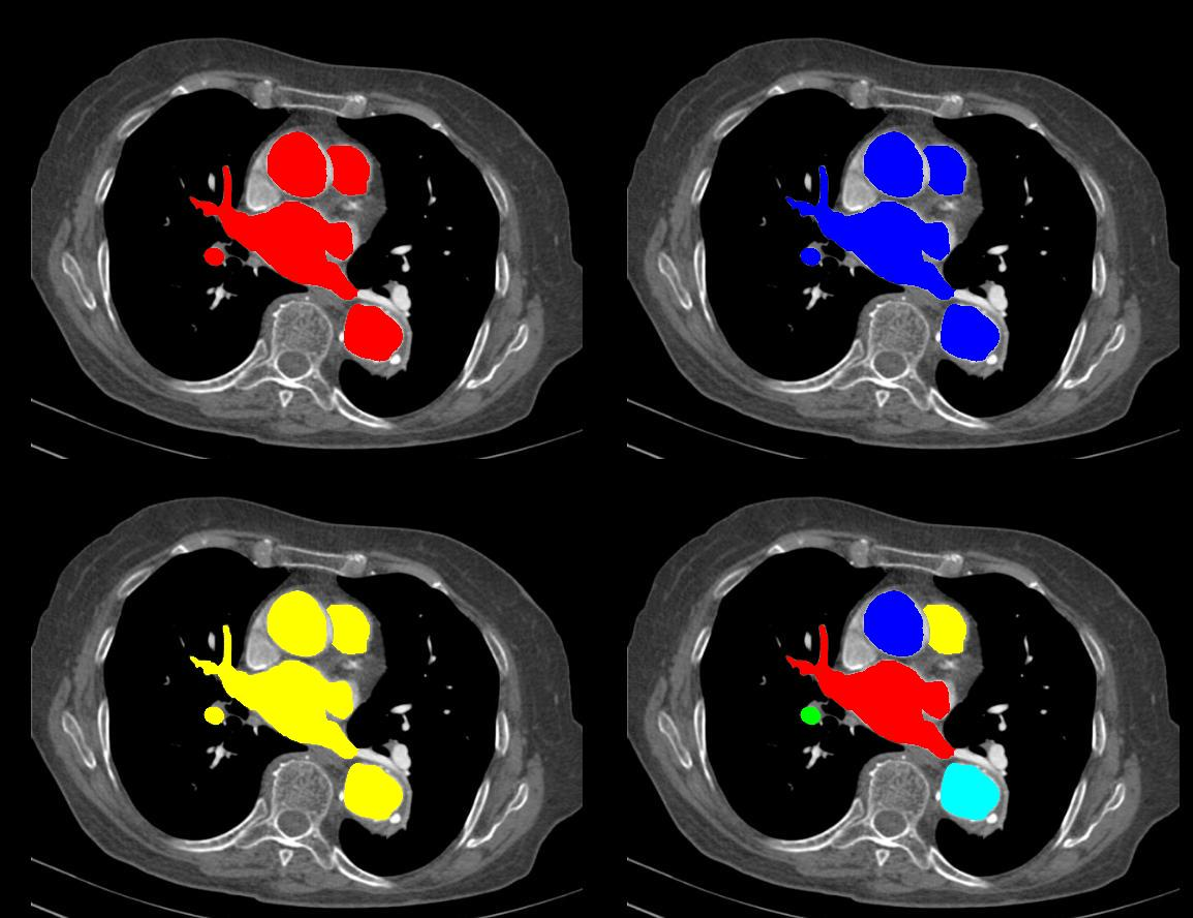

今天不飞了,一起写代码吧。做图像分割、目标检测、物体识别的老铁都会遇到,在得到结果之后需要显示mask或label,为了简便经常就直接imshow了。有时候这样做并不是那么直观,今天就给大家分享一种直接在原图上利用伪彩色高亮分割结果的方法(如下图)。

在这里插入图片描述

这个例子只有5个标签,要是有50个……